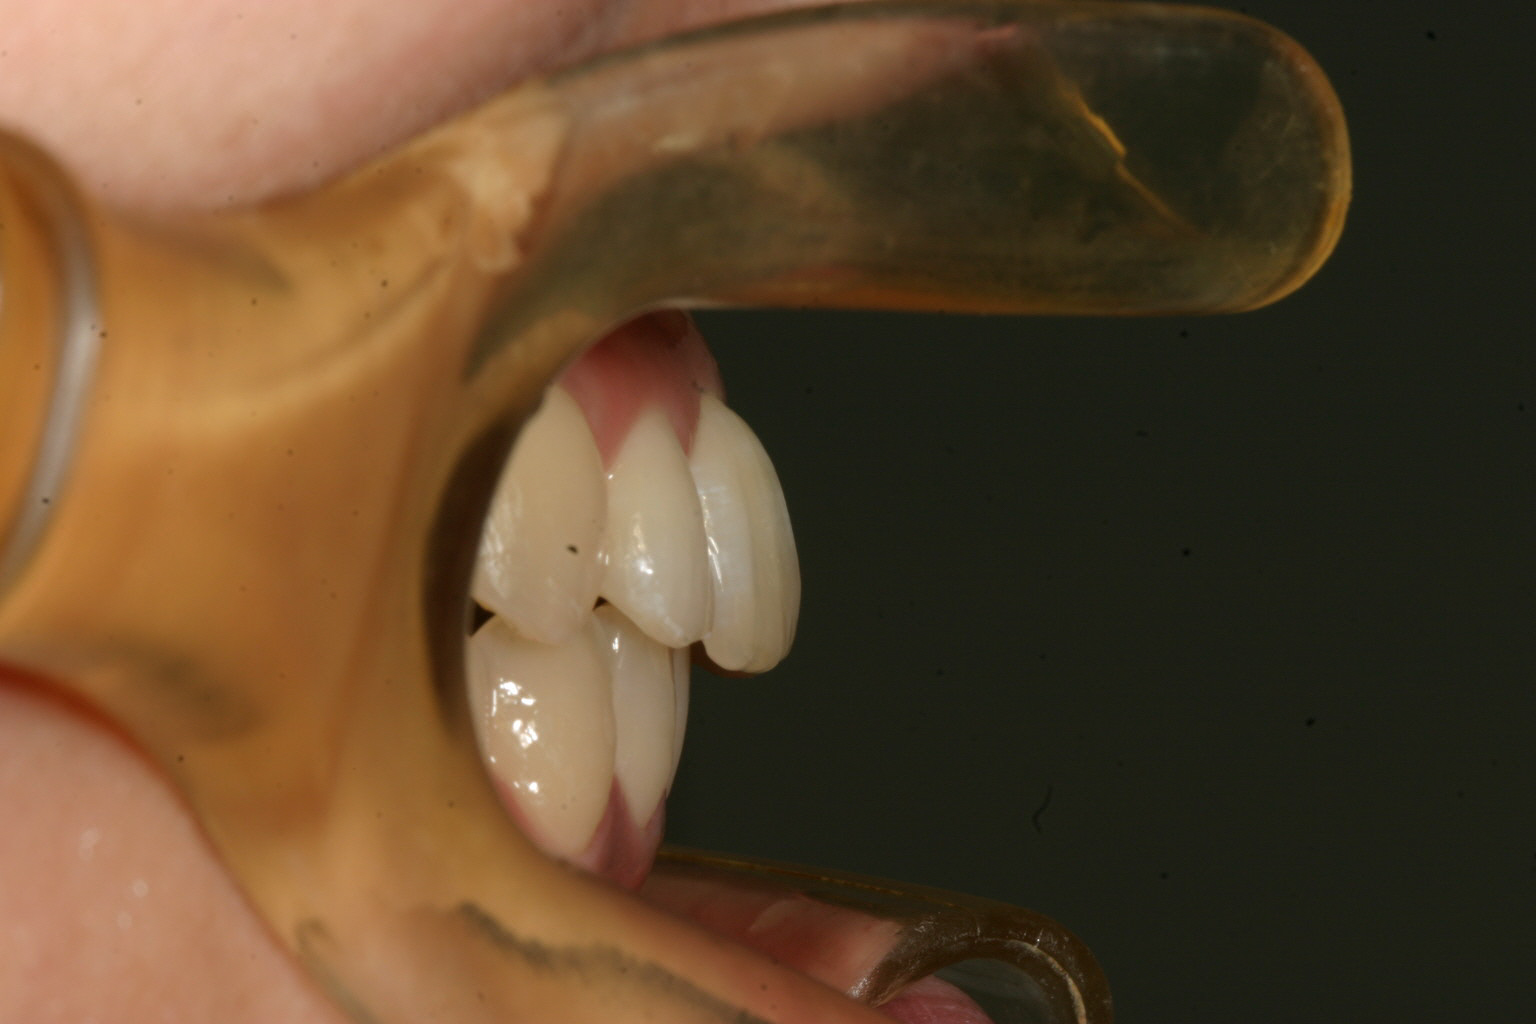

ちょっと出っ歯感が大きいですね~

上の写真と比べてください。 抜歯もせずにここまで綺麗になりました。

当院では出来る限り抜歯矯正は避けたいと言う考えで矯正を行っています。

そういう考えに同調して頂ける患者様は歓迎です。